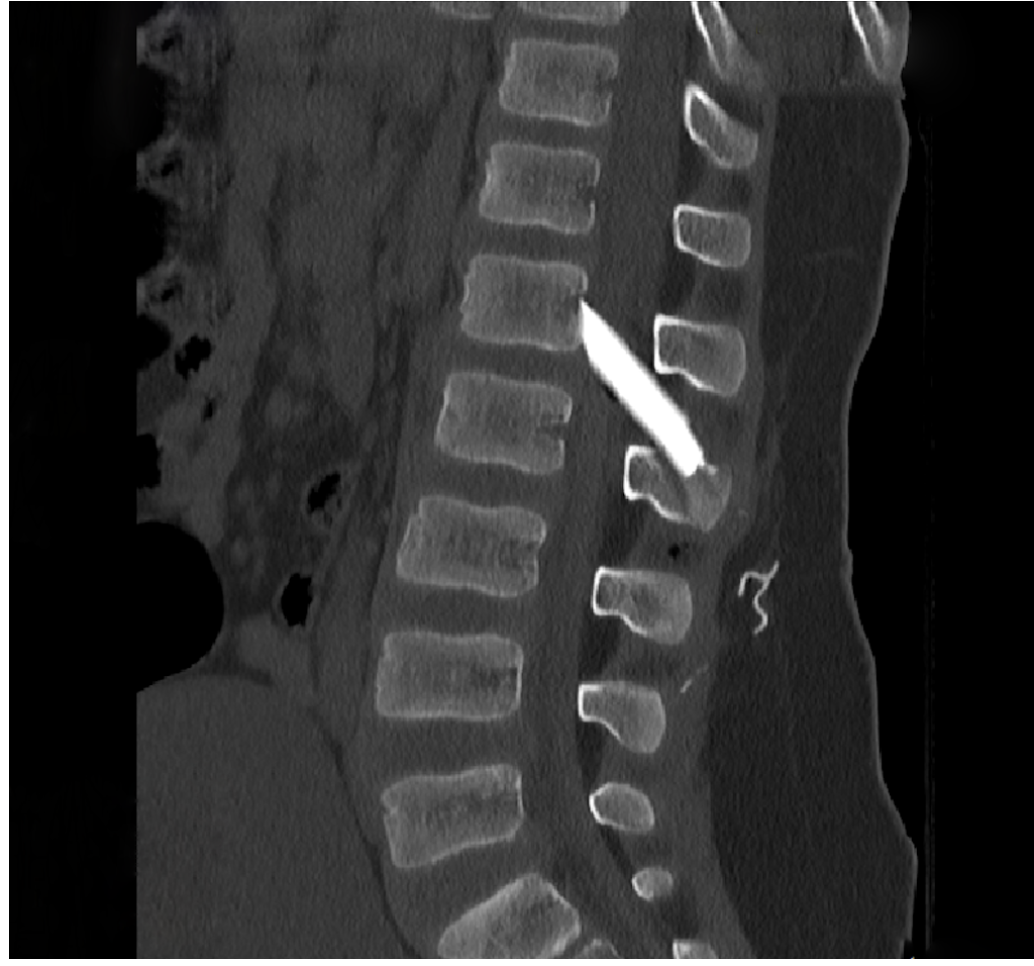

image_1_1.pngΟι μαγνητικές και αξονικές τομογραφίες πραγματοποιήθηκαν άμεσα, επιβεβαιώνοντας τις αρχικές υποψίες: δύο μεγάλα κομμάτια γυαλιού είχαν ενσφηνωθεί στη σπονδυλική στήλη, εισχωρώντας εντός του σπονδυλικού σωλήνα σχίζοντας την ιππουρίδα και την μήνιγγα που την περιβάλλει.

Ακολούθησε άμεση εισαγωγή του παιδιού στο χειρουργείο, όπου με πολύ προσεκτικούς χειρισμούς και τη χρήση προηγμένου εξοπλισμού, όπως το σύστημα χειρουργικής πλοήγησης, πραγματοποιήθηκε επιτυχής αφαίρεση όλων των κομματιών γυαλιού μετά από ένα πολύωρο και απαιτητικό χειρουργείο.